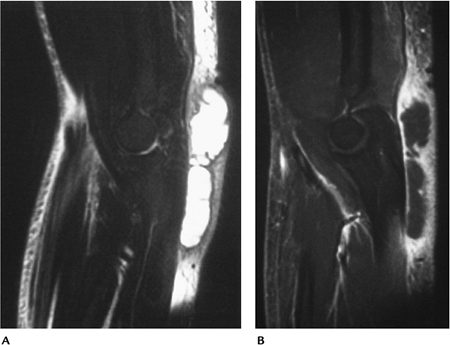

![]() |

FIGURE 8-30 Soft tissue abscess. Sagittal T2-weighted (A) and post–gadolinium-enhanced fat-suppressed (B) images showing a large nonenhancing fluid collection.

P.553

FIGURE 8-31 Sagittal T1- (A) and T2-weighted (B) images demonstrate diffuse soft tissue edema and abnormal signal intensity in the ulna due to osteomyelitis.

Infection

Musculoskeletal infections may present as an acute or insidious process.

Skeletal infections typically present in medullary bone with hyperemia and edema.

Soft tissue infections may be diffuse or result in more localized abscess formation.

Joint space infections may present with soft tissue changes, joint effusion, or joint and bone involvement.

Routine radiographs usually are normal